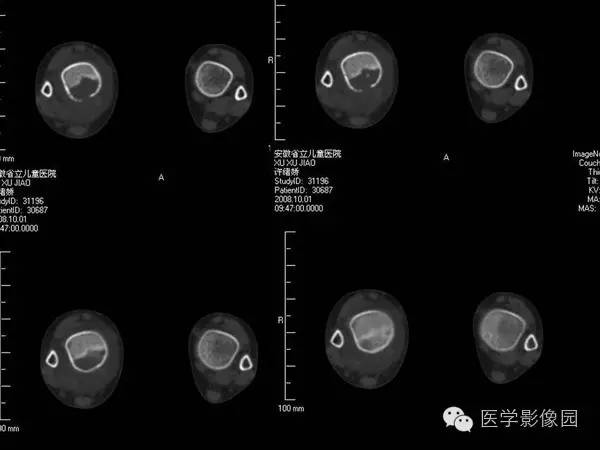

【病例】浆细胞性骨髓炎1例X线及CT影像表现